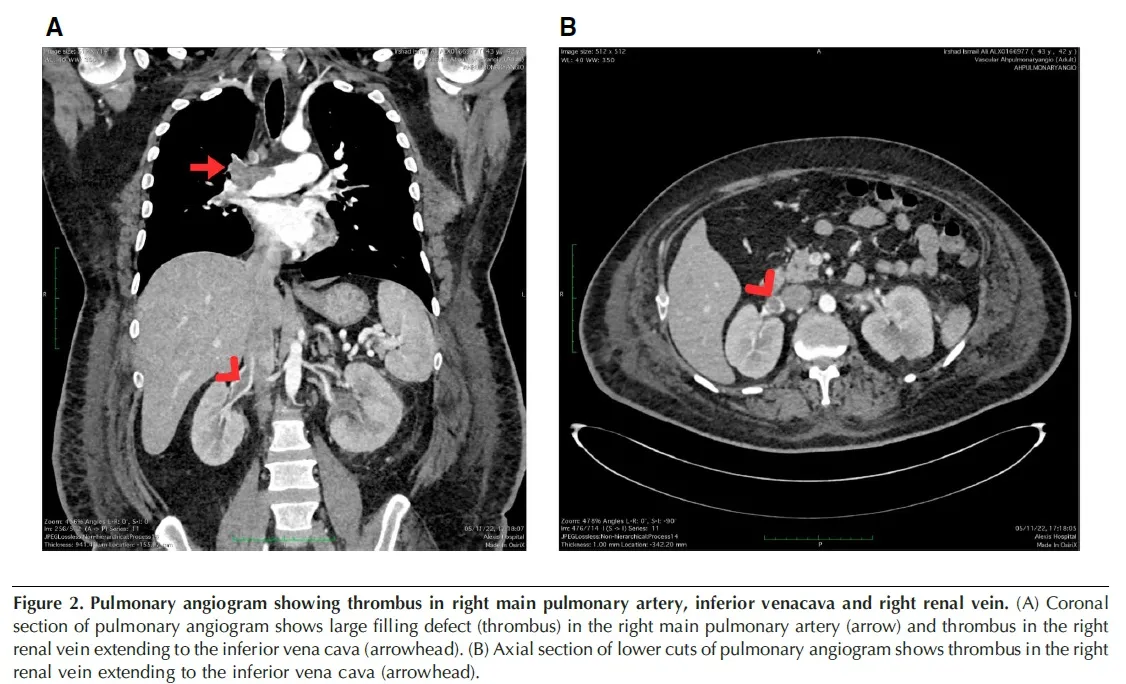

Um dia após a biópsia, o paciente apresentou dispneia súbita, taquicardia e hipotensão. Ecocardiograma revelou dilatação do tronco da artéria pulmonar e do ventrículo direito. A tomografia computadorizada de tórax confirmou tromboembolismo pulmonar associado a trombose da veia cava inferior e veia renal direita. Foi realizada trombólise com alteplase, sem intercorrências hemorrágicas, seguida de anticoagulação com rivaroxabana.